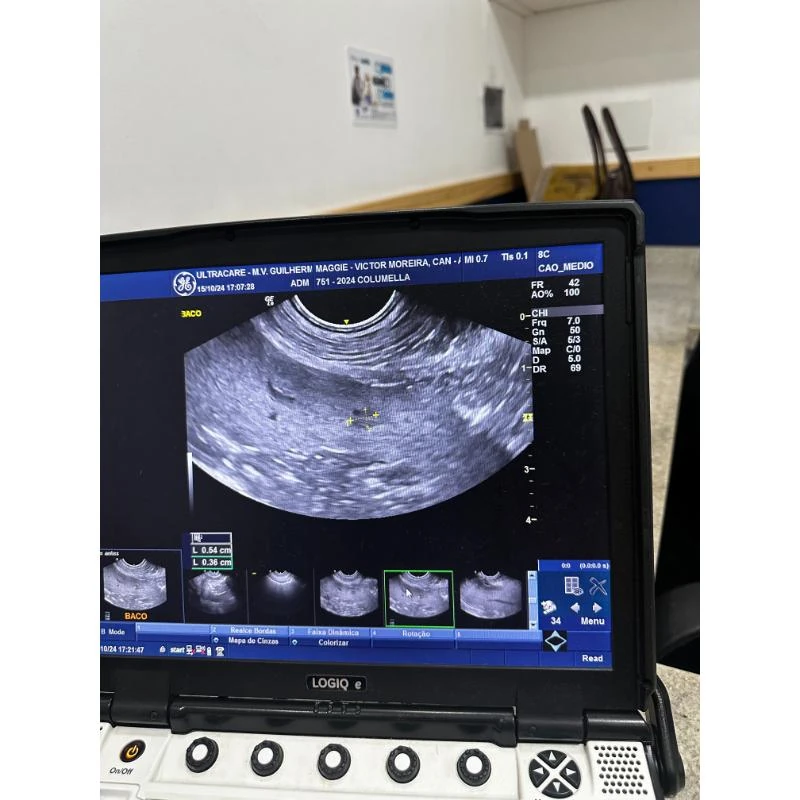

A ultrassonografia animal é um exame fundamental para a saúde e bem-estar dos pets, permitindo uma análise completa de órgãos e tecidos de cães, gatos e pequenos animais.

Na Columella Centro Veterinário, localizada em Juiz de Fora (MG), esse procedimento é realizado com qualidade consistente, oferecendo resultados rápidos e um acompanhamento detalhado do tutor.

A ultrassonografia animal é um exame de imagem não invasivo que utiliza ondas sonoras de alta frequência para visualizar estruturas internas do corpo do animal.

Essas ondas sonoras são emitidas por um transdutor e, ao atingirem os órgãos e tecidos, retornam em forma de imagens em tempo real.

Dessa forma, é possível avaliar o funcionamento e a saúde de órgãos como fígado, rins, baço, intestinos, entre outros.

Além disso, é uma ferramenta essencial para o diagnóstico de diversas condições, como tumores, inflamações, cistos, gestações, entre outras patologias.

Com a realização desse exame, os veterinários conseguem obter informações precisas sobre a saúde do animal e direcionar o tratamento adequado.

A ultrassonografia veterinária na Columella Centro Veterinário permite uma avaliação detalhada de órgãos internos, tecidos e sistemas, oferecendo um diagnóstico rápido e preciso.

Esse exame é conduzido por uma equipe especializada, que promove um acompanhamento contínuo do tutor e atenção ao bem-estar do animal.

Com uma estrutura de alto padrão e equipamentos modernos, a Columella Centro Veterinário se destaca pelo atendimento 24 horas e pela qualidade consistente em cirurgias e internações veterinárias.